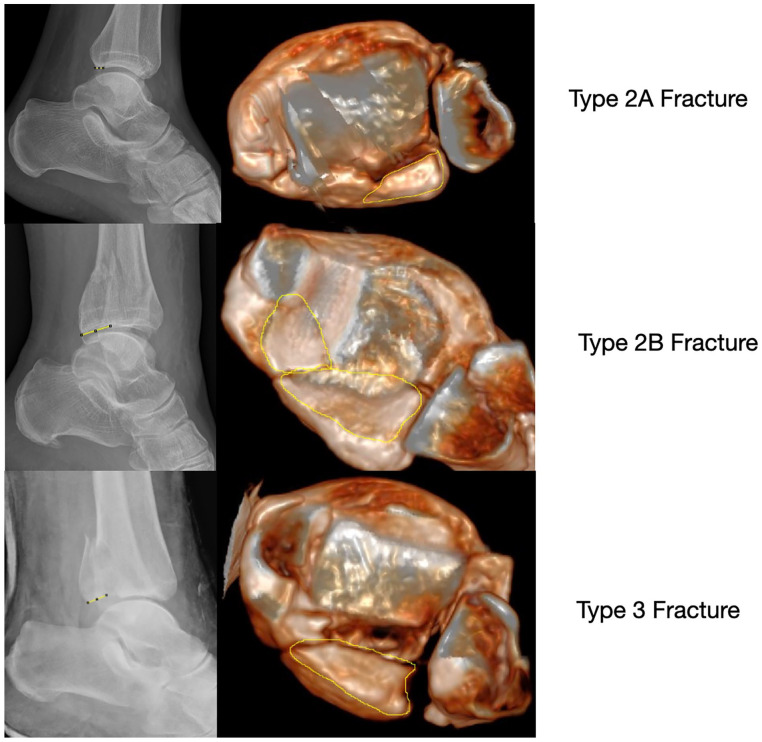

Methods: Morphology of the PMF was categorized initially by the CT scan as classified by Mason and Molloy on 180 trimalleolar ankle fractures. PM fracture fragment size on the lateral radiograph were compared to their respective 3D surface rendering CT reconstructions, by two independent observers. Morphology of the PMF was assessed using all preoperative radiographs as compared to 3D SR CT.

Results: On comparison of fracture fragment morphology, all fractures had poor categorization by plain radiographs although rotational pilon fractures (type 2A and 2B fractures) had the worse sensitivity and specificity (below 33% and below 50%, respectively). Radiographs underestimated joint involvement in type 2B fracture patterns because of the underappreciation of the posteromedial fragment.

Conclusion: This study shows that the use of plain radiographs to categorize morphology of PMFs is poor. The study adds to the ever-growing body of evidence on the inaccuracy of using plain radiographs in PMFs to plan treatment. Additional CT imaging is imperative to allow for appropriate treatment planning in the management of PMF. Smaller fracture fragments are more susceptible to inaccuracies, especially the rotational pilon subtypes (2A and 2B) because of the obliquity of the posteromedial fragment to the plane of the X-ray source.